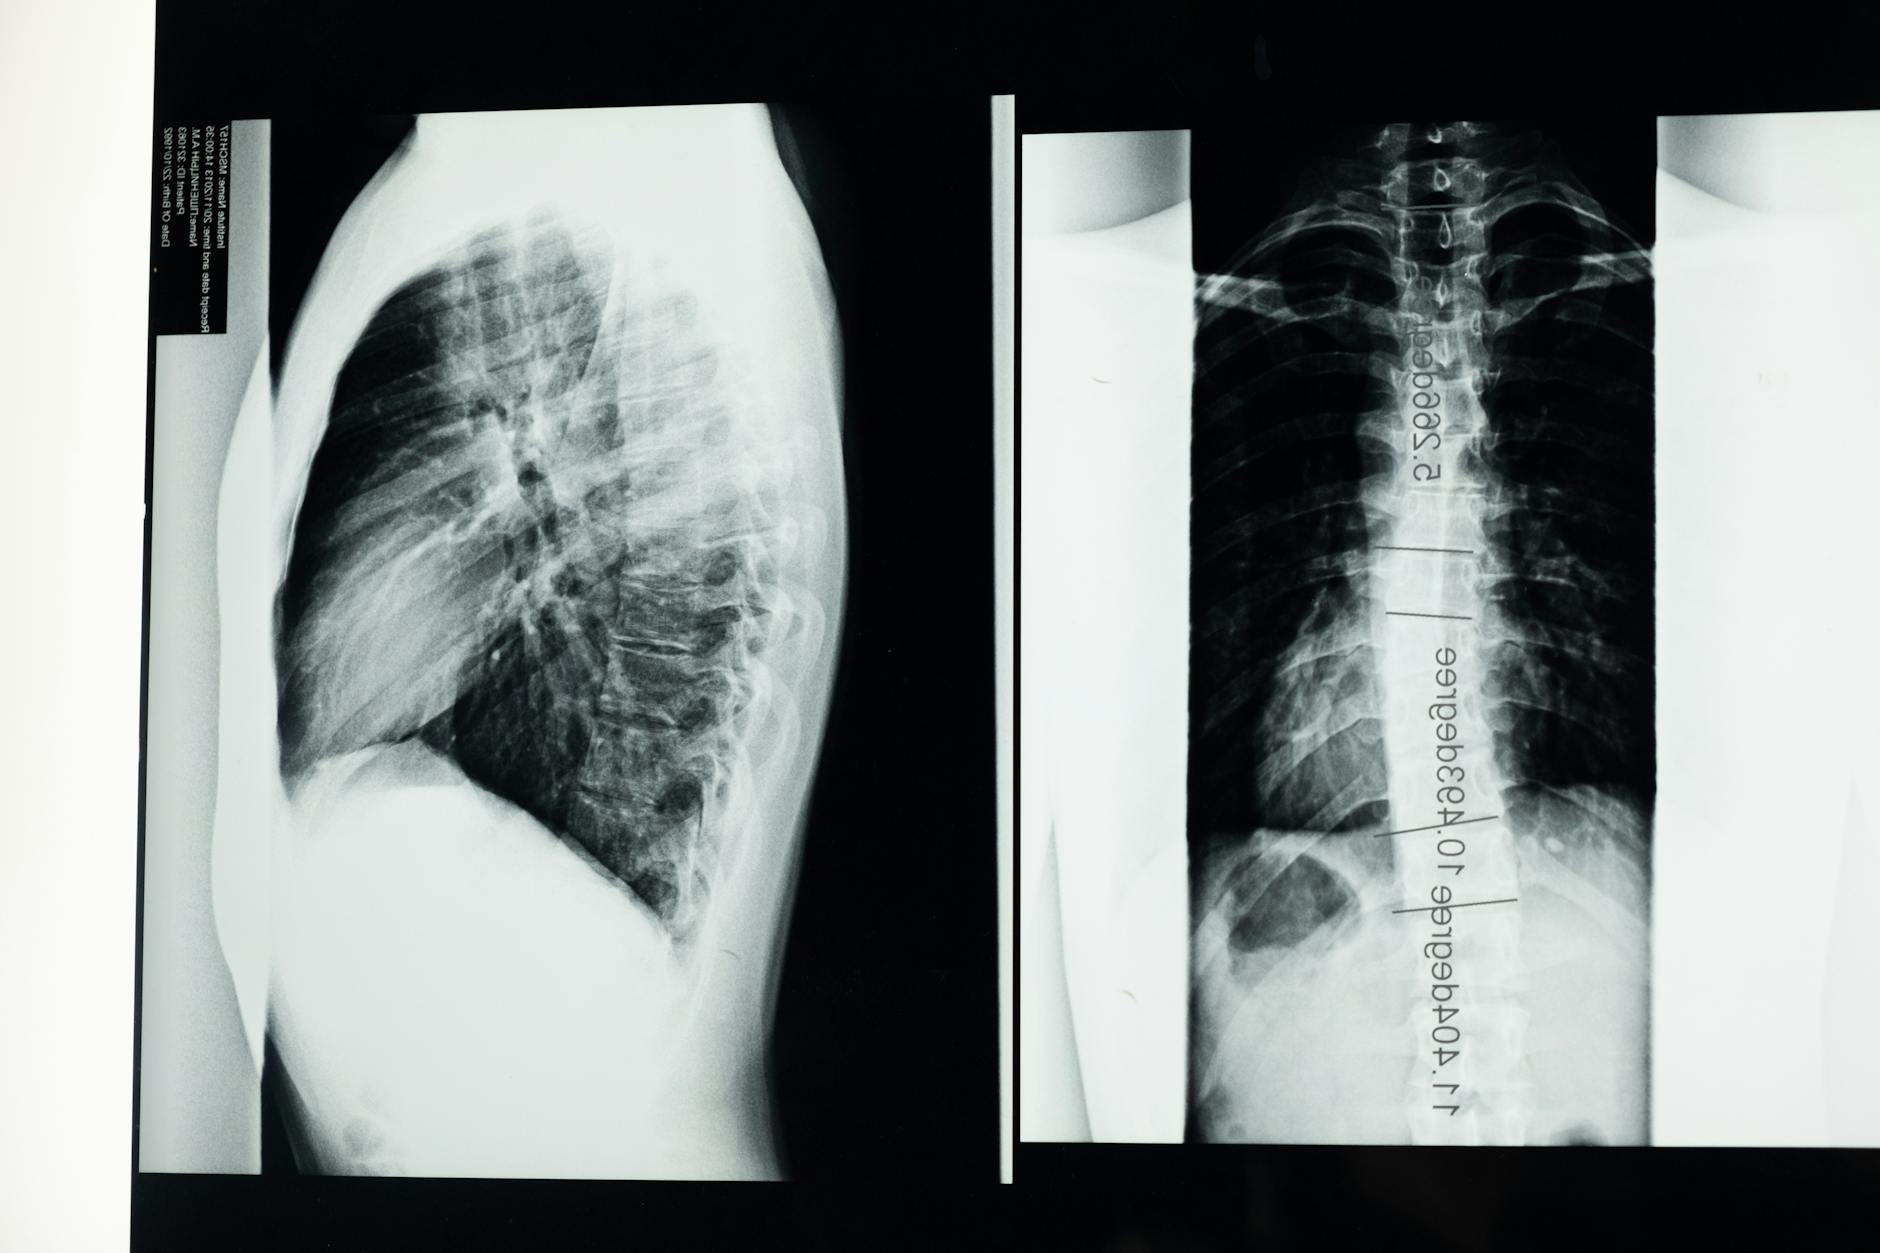

- Badania diagnostyczne – badanie krwi (poziom wapnia, fosforu, witaminy D3, hormon PTH), RTG kości

- Widoczne deformacje kości – skrzywienia kręgosłupa (skolioza, lordoza), zniekształcone kończyny

- Złamania patologiczne – kości łamią się przy minimalnym wysiłku lub bez widocznej przyczyny